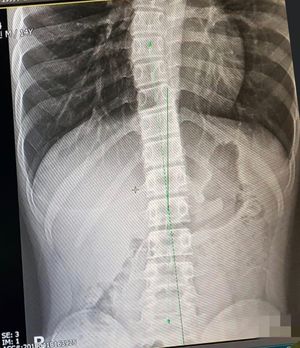

애덤스 전방 굴곡 검사[74]나 스코리오미터[75]를 사용하여 척추측만증을 진단할 수 있다. 척추측만증이 의심되면, 체중 부하 상태에서 척추 전체의 전후면(AP)/관상면 X-레이(정면-후면) 및 시상면 X-레이(측면)를 촬영하여 척추측만증의 만곡과 후만증, 전만증을 평가한다.[76] 성장기 환자의 경우, 곡선 진행을 추적하기 위해 3~12개월 간격으로 척추 방사선 촬영을 하며, 필요한 경우 MRI 검사를 통해 척수를 관찰한다.[76]

콥 각도는 척추 만곡의 정도를 측정하는 표준 방법으로, 관련된 가장 위쪽 척추의 상단 종판에 수직으로 그려진 두 선과 관련된 가장 아래쪽 척추의 하단 종판 사이의 각도를 측정한다. 척추측만증 연구 학회(SRS) 등에서는 관상면에서 10° 이상의 콥 각도를 척추측만증으로 정의한다.[83]

렌트겐 사진 등에서 만곡의 정도(콥 각/Cobb angle)를 측정하여 대략

- 경도(25도 미만)

- 중도(20도~40도 정도)

- 고도(50도 이상)

의 세 단계로 분류하며, 경도에서는 정기적인 X선 촬영을 통한 경과 관찰을 지속한다.